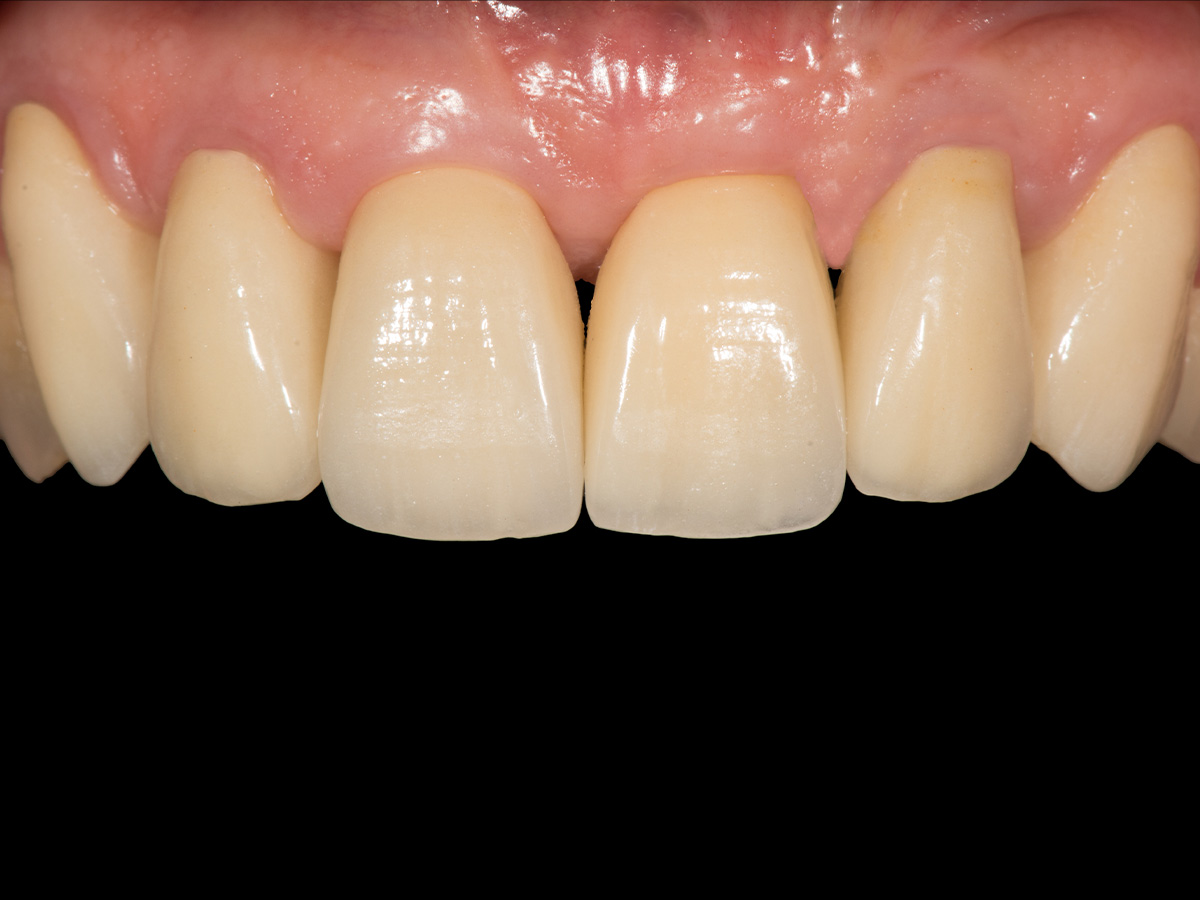

Abbildung 15

Abschlussfoto.